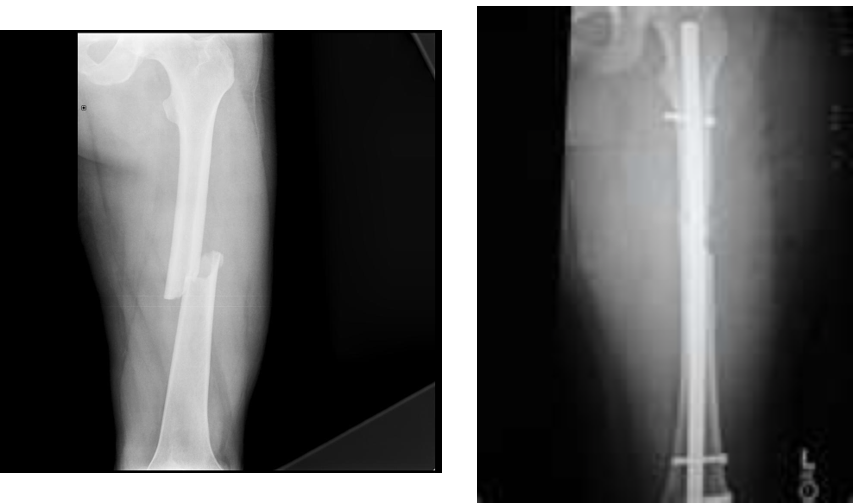

Q

Management of femoral shaft fractures

A

1. Thomas splint for temporary stabilisation

2. closed reduction + IM nail / plate fixation

Investigations for femoral shaft fractures

Xray